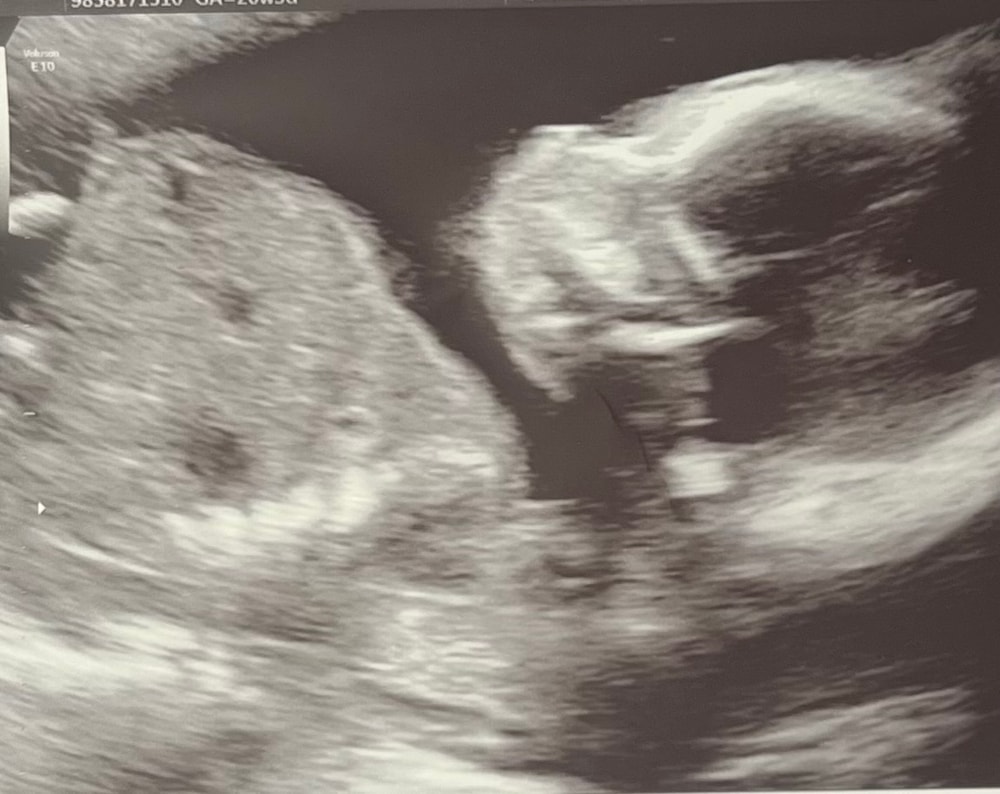

Второй скрининг пройден ✅

УЗИ, КТГ, доплерВторой скрининг пройден без проблем 🙏🏼

Подтвердили, что будет девочка 💕😍

📏 Показатели малыша:

• Ширина головы — 47 мм

• Окружность головы — 178 мм

• Живот — 149 мм

• Бедренная кость — 32 мм

• Вес малышки — 335 г 😍